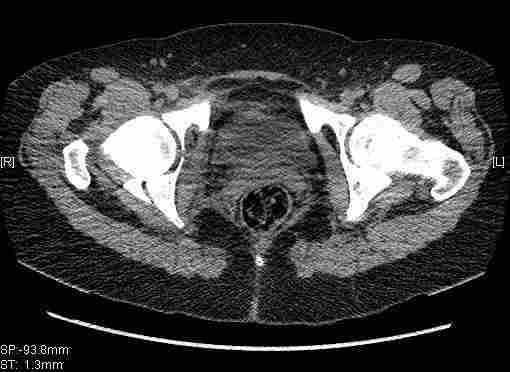

Женщина,58 лет, после ДТП 6 суток. Первично повреждение расценено как переломы ветвей лонной кости. После подтверждения повреждения вертлужной впадины,как чаще всего случается, вопрос встал о тактике. БОльшинство за консерватиное лечение.К сожалению кт у нас "во время" сломался. Прилагаю стандартные снимки вертлужки. У меня следующие вопросы к коллегам:1. Правильно ли рассценивать это повреждение как Т-образный перелом вертлужнй впадины?2. Можно ли добиться анатомической репозиции поверхности вертлужной впадины скелетным вытяжением в данном случае, если нет, что будет этому препятствовать?3. Если смещение останется таким как сейчас, через какое время появится необходимость эндопротезирования (по вашему опыту)?Спасибо.

Уважаемый Коваленко А.Н., снимки плохого качества и нет уверенности, что задняя колонна сломана (смещена). Если кт нет - везите больную в рентгенкабинет (палатником качественные снимки снимки не получатся) и сделайте обзорный снимок таза, Judet и может быть inlet, хуже вы ей не сделаете.

Удалось сегодня вывести пациентку в соседнюю больницу, где есть кт. Срезы сделаны только горизонтальные.